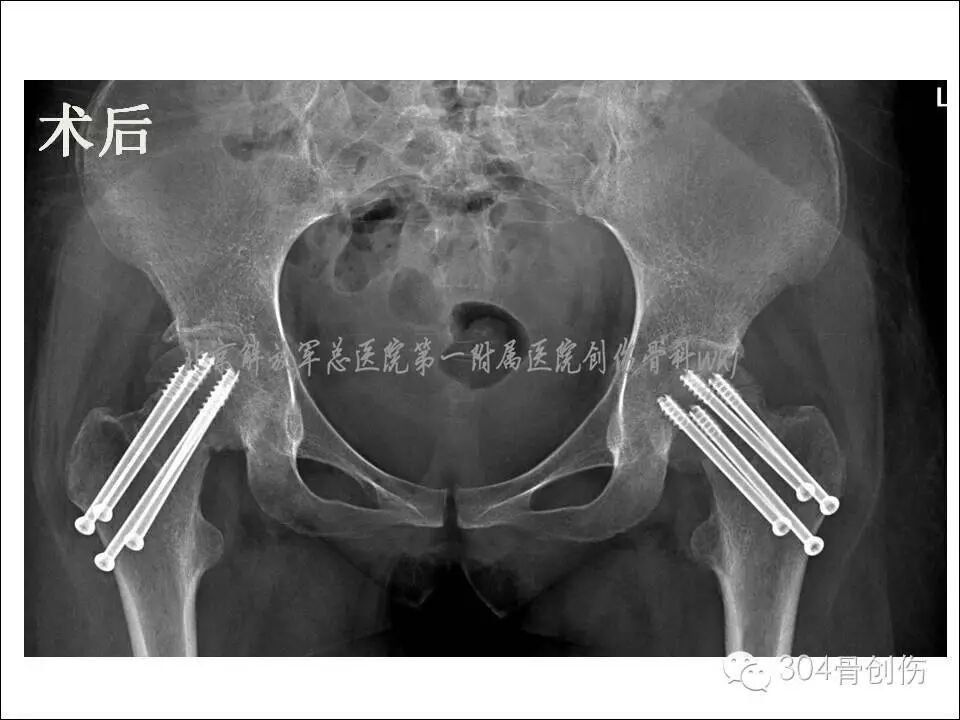

全麻下双侧股骨颈骨折闭合复位内固定。在C型臂透视下,牵引床辅助闭合复位,固定股骨头、下肢极度内旋,骨折复位满意,为增加固定强度,双侧各经皮打入4枚空心螺钉(图)。术后口服钙尔奇600mg每天2次,骨化三醇胶丸0.25ug 每天3次。双腿非负重活动。

术后6个月患髋部X线显示,股骨颈有短缩,螺钉少许退钉,骨折基本愈合,骨折愈合左侧优于右侧。术后1年,股骨颈未继续缩短,左侧股骨颈完全愈合,右侧股骨颈略差,行走时右髋偶感不适。术后2年随访时(图),双侧股骨颈骨折愈合,患者步态正常(图)。

图-术后X线片

图-术后两年X线片